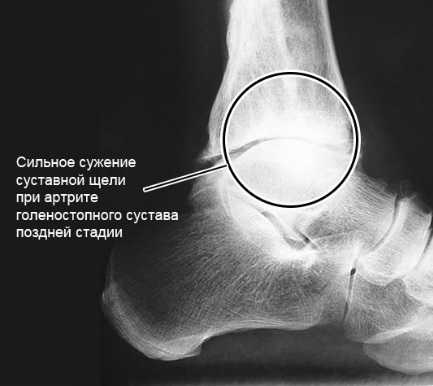

- высокоинформативные визуализирующие методы (УЗИ, МРТ) — ниже артрит на МРТ;

Заподозрить воспаление позволяют характерные симптомы: боль, отечность, покраснение кожи в области голеностопного сустава. При сопутствующем поражении синовиальной оболочки у человека появляется утренняя скованность и тугоподвижность ГС. Если артрит прогрессирует и приводит к дегенеративным изменениям хрящей и костей, у больного нарушается подвижность сустава.

Артрит голеностопа на МРТ.

Чтобы выяснить причину воспаления, проводят лабораторные и иммунологические исследования. Для каждого вида артрита характерны свои изменения в анализах крови и синовиальной жидкости. При остром гнойном воспалении выявляют экссудат в синовиальной полости и нейтрофильный лейкоцитоз в крови. А при ревматоидном артрите обнаруживают высокие уровни ревматоидного фактора и АЦЦП.

Для определения стадии заболевания используют визуализирующие инструментальные методы. При острых и начальных стадиях хронических артритов информативны только УЗИ и МРТ. С их помощью можно обнаружить практически любые изменения в суставах и околосуставных тканях. На поздних стадиях, когда происходит массивное разрушение костей, достаточно информативна и рентгенография. Она позволяет обнаружить характерные для артроза изменения: сужение суставной щели, остеофиты, субхондральный остеонекроз, признаки остеопороза и т.д. При остром артрите рентгенография может выявить неравномерное сужение суставной щели, которое косвенно указывает на скопление гноя.